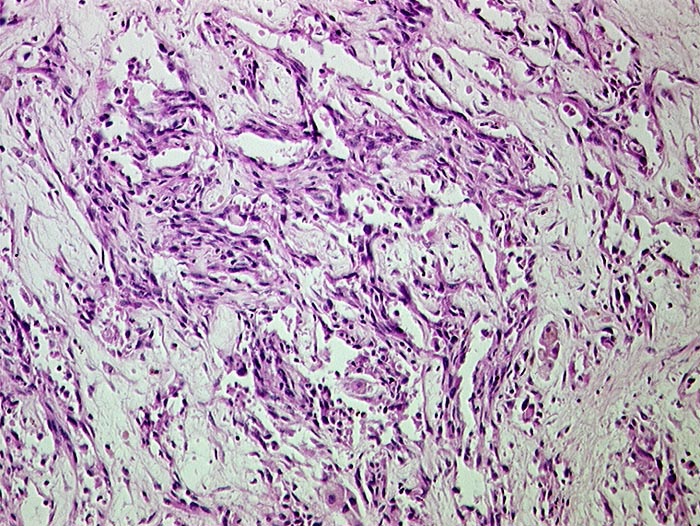

Angiosarkom

maligner Tumor

Leber

Gefässräume ausgekleidet durch atypisches Endothel.

Histologie